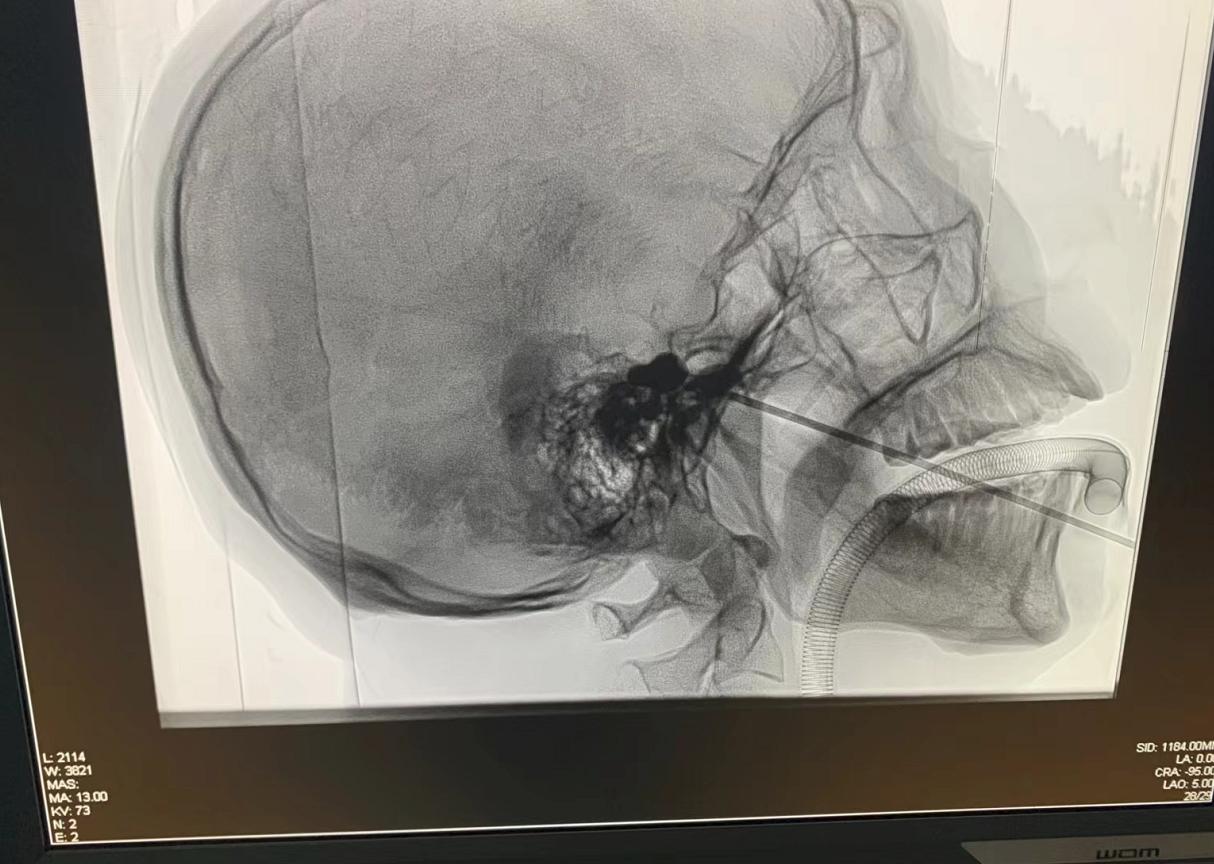

手术由肖鸿智主任医师主刀,刘柏京副主任医师做一助,颜望鹏主治医生密切配合,在麻醉医师的配合下全麻下进行,术中在DSA引导下经口角外侧的面部穿刺点,穿刺针精准穿刺患者左侧卵圆孔,针芯内植入球囊导管,施行球囊压迫半月神经节。手术仅用时30分钟,睡个觉的功夫,术后李奶奶疼痛立即消失。

郴州市第一人民医院疼痛科疼痛科主任肖鸿智介绍,“三叉神经半月节球囊压迫术”也称“针尖内的手术”,整个创口仅一个针眼大小,在透视下确认穿刺方向和位置正确,然后在半月节位置导入球囊导管,压迫三叉神经感觉根特定位置,从而使三叉神经痛觉纤维失活,达到治疗三叉神经痛的目的。该术式时间短、效果明显、复发率低、术后恢复快,尤其适用于年老、体弱、有严重系统疾病或拒绝开颅手术的患者。